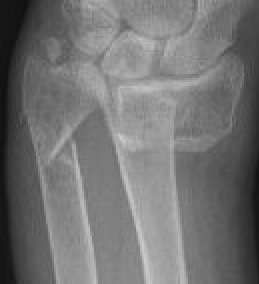

DRUJ instability after distal radius fracture

1. Ulna styloid fracture

2. No ulna styloid fracture / TFCC injury

Ulna styloid fractures occur in half of all distal radius fractures

Classification ulna styloid fractures

| Type 1: Tip | Type 2: Base | Type 3: Proximal to styloid |